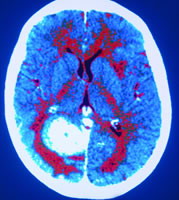

血管新生是人體內許多正常生理活動的基礎,對於腫瘤的生長和轉移也非常重要。血管新生是一個受到嚴密調控的多步驟過程,其中血管內皮細胞的遷移是關鍵一環。周軍課題組博士生高金珉等人前期的研究發現,CYLD通過其CAP-Gly結構域與微管細胞骨架相互作用,調節微管的組裝和穩定性,從而有利於細胞的遷移,2008年發表在《生物化學雜誌》(Journal of Biological Chemistry)上。

在本項研究中,高金珉等人在他們前期工作的基礎上,發現CYLD通過對血管內皮細胞中微管的動態性進行精細調節,刺激Rac1的活化,介導血管內皮細胞的極化和遷移,從而促進新血管的形成。該項研究發現了CYLD調節血管新生過程的一個新功能,加深了對微管及其相關蛋白功能和調控機制的理解。該項工作得到國家自然科學基金、科技部重大科學研究計畫及天津市科委項目的資助。